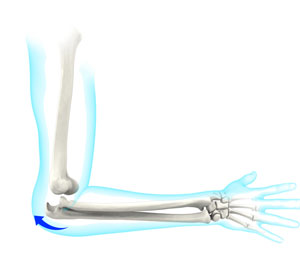

The arm in the human body is made up of three bones that join to form a hinge joint called the elbow. The upper arm bone or humerus connects from the shoulder to the elbow to form the top of the hinge joint. The lower arm or forearm consists of two bones, the radius, and the ulna. These bones connect the wrist to the elbow forming the bottom portion of the hinge joint.

The bones are held together by ligaments to provide stability to the joint. Muscles and tendons move the bones around each other and help in performing various activities. Elbow dislocation occurs when the bones that make up the joint are forced out of alignment.